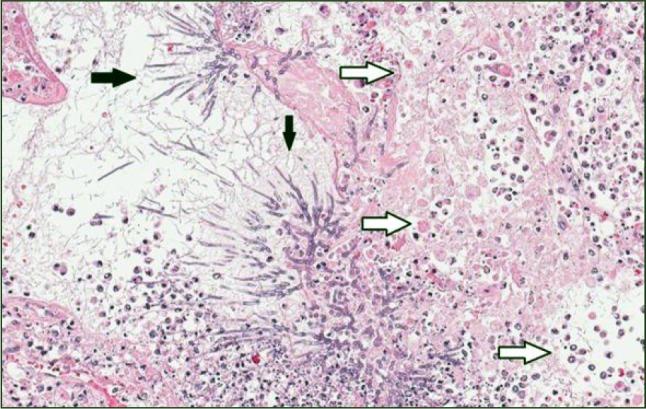

ANCA-associated vasculitis (AAV) is an inflammatory systemic disorder affecting small to medium sized vessels and likely leading to any organ dysfunction. Adequate treatment is important to avoid mortality or severe organ damage. In most cases initial treatment (induction therapy) allows to achieve remission. Induction therapy leads to immunosuppression and may cause severe infections. However, in vasculitis patients even an intensive immunosuppressive therapy is rarely complicated by an invasive fungal infection. We present a case in a 29-year old male patient with newly diagnosed AAV. He suffered a fatal pulmonary complication of the induction immunosuppressive treatment. Pathological (infectious) changes in the lungs were misinterpreted as progression of the vasculitis and he died due to disseminated angioinvasive aspergillosis. A clinical course, imaging and histopathology of this case are described and discussed.

抗中性粒细胞胞浆抗体相关性血管炎(AAV)是一种影响中小血管的炎症性全身性疾病,可能导致任何器官功能障碍。充分的治疗对于避免死亡或严重器官损害很重要。在大多数情况下,初始治疗(诱导治疗)可实现缓解。诱导治疗会导致免疫抑制,并可能引起严重感染。然而,在血管炎患者中,即使是强化免疫抑制治疗也很少并发侵袭性真菌感染。我们报告一例29岁新诊断为AAV的男性患者。他在诱导免疫抑制治疗中出现了致命的肺部并发症。肺部的病理(感染性)变化被误诊为血管炎的进展,他因播散性血管侵袭性曲霉病死亡。本文描述并讨论了该病例的临床病程、影像学和组织病理学情况。